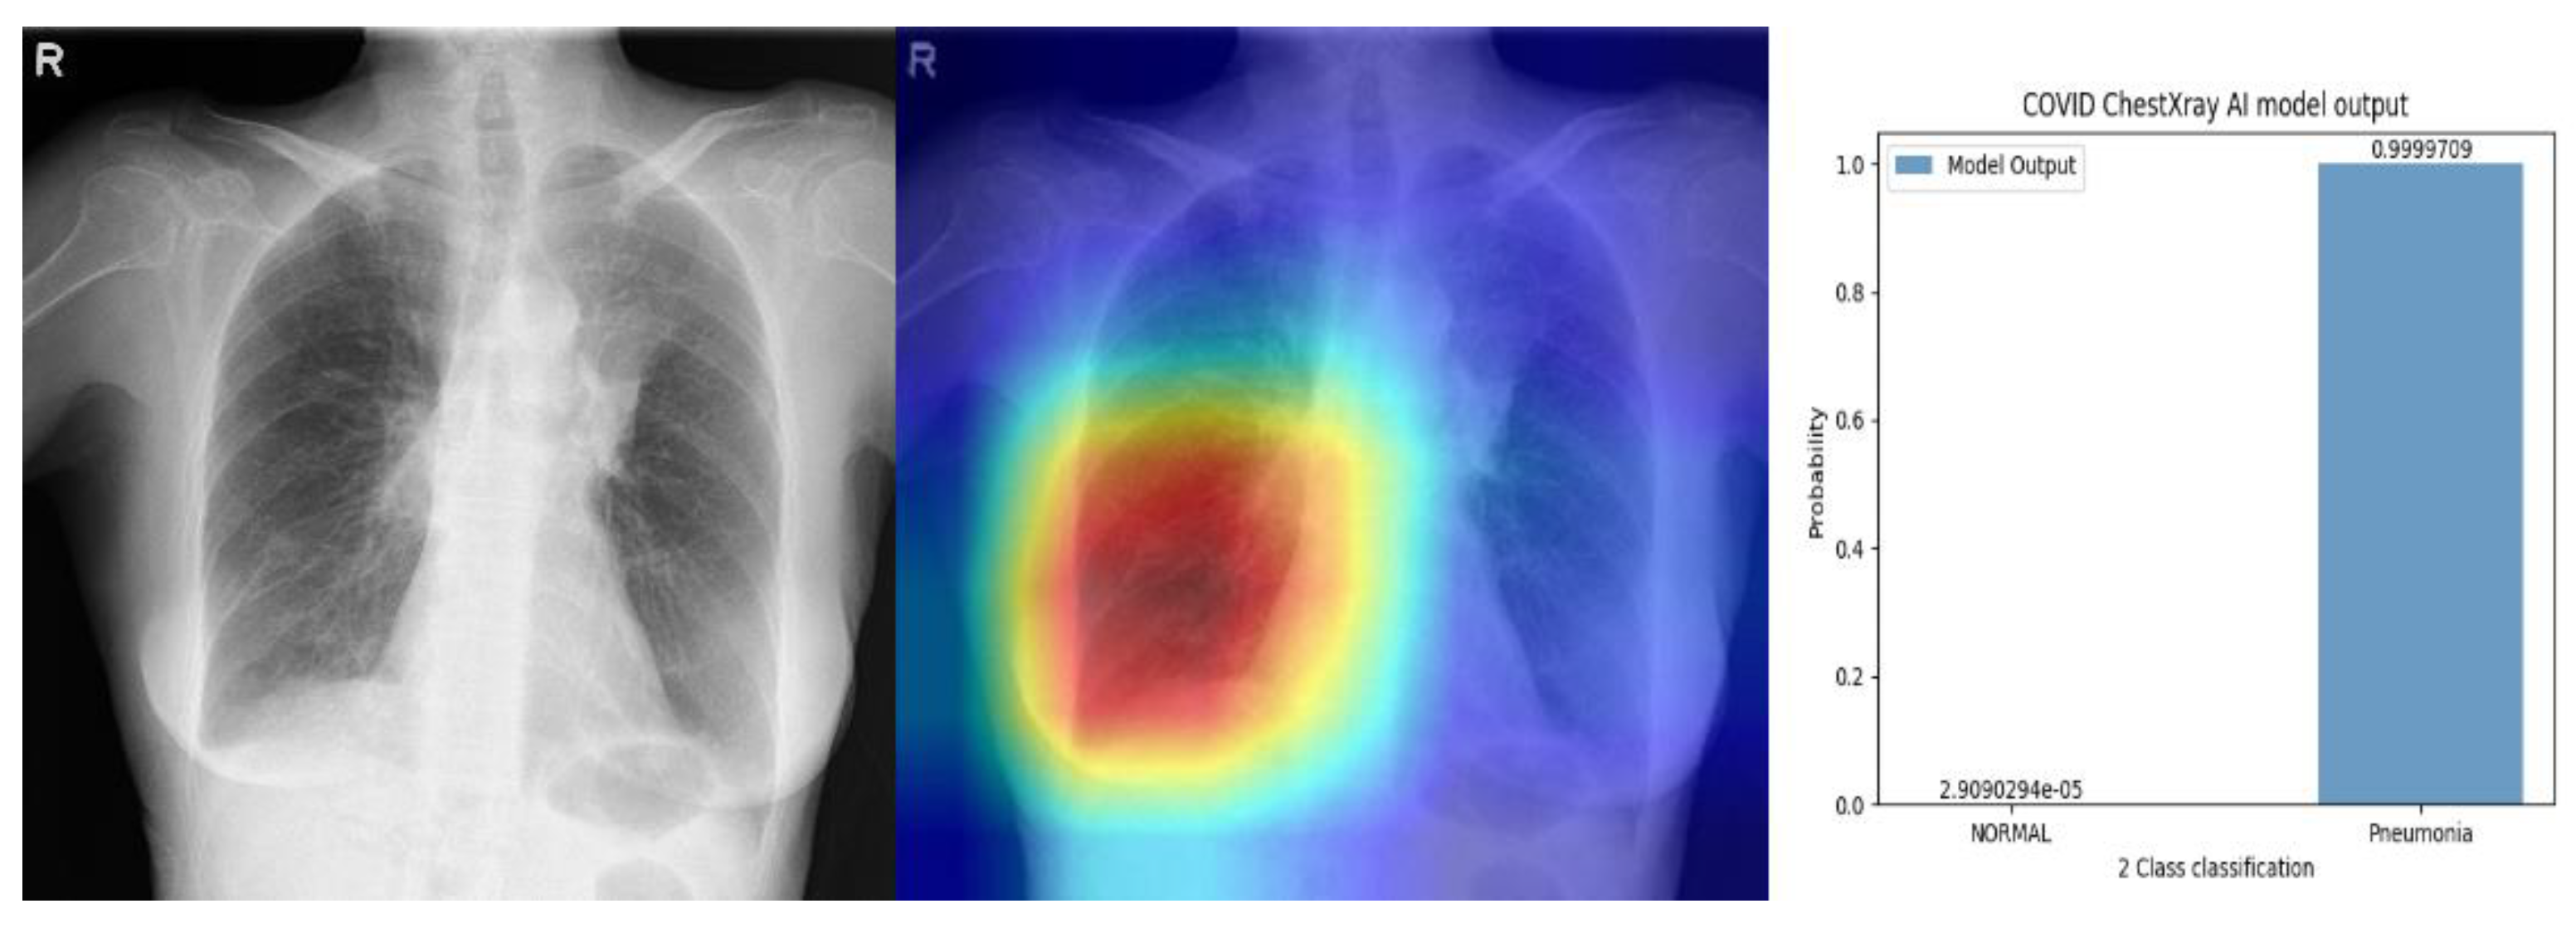

Appendix C. Examples Using Saliency Maps and Probability Output